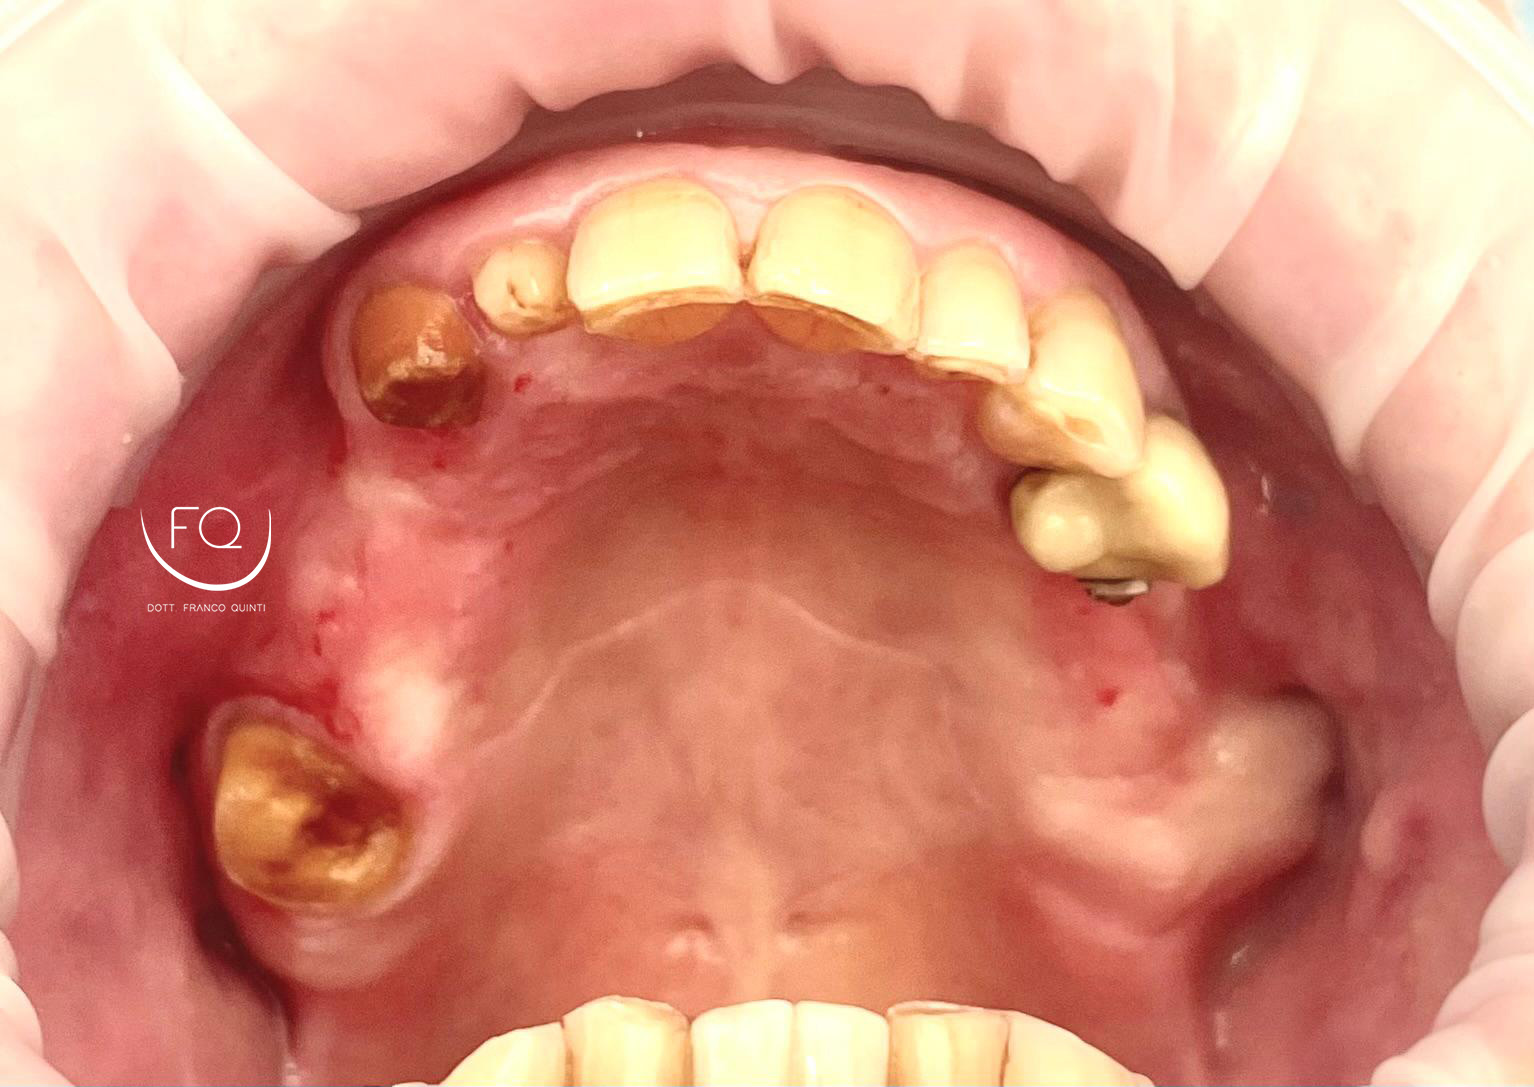

Questa settimana vi presento un caso di chirurgia computer guidata dell’arcata superiore realizzata con dima scomponibile doppia.

Nell’intervento sono stati inseriti 6 impianti PRAMA di Sweden & Martina con contestuale esecuzione del carico immediato.